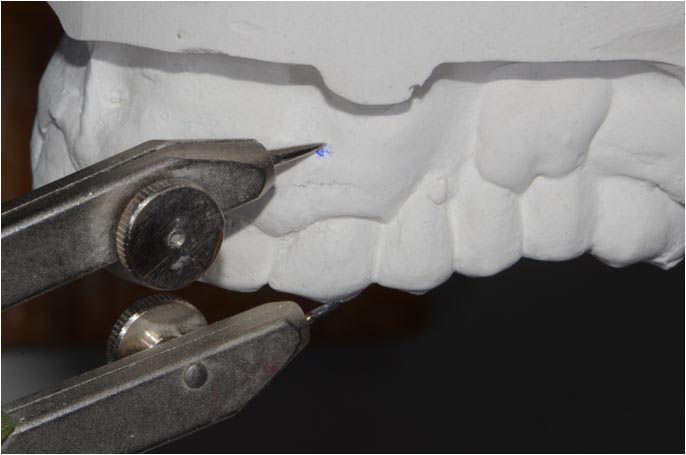

Diagnostic wax-up: the incisal margin is modified to mount the models in centric relation with the maximum intercuspation.

To achieve tooth elongation it is necessary to establish position, length, shape and size starting from the incisal edge of the two central incisors.